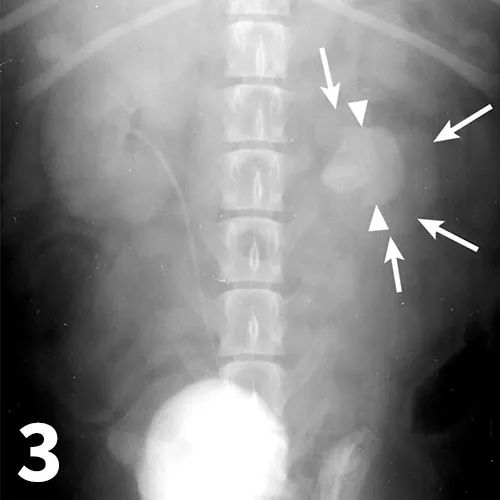

Survey abdominal radiographs (Figures 1 and 2) offer important information on kidney number, size, shape, symmetry, and location, as well as the presence of any mineralized opacities (eg, calcified tissue, nephroliths). The utility of abdominal radiographs is decreased in patients with abdominal fluid or lack of abdominal fat (eg, young or emaciated patients) because of lack of contrast. Excretory urography (IV pyelography), although more invasive, can augment survey radiographs and provide information about renal parenchymal architecture (eg, filling defects associated with cysts or infiltrative disease), the renal pelvis, and ureters as well as a qualitative assessment of global and individual renal excretory function (Figure 3).